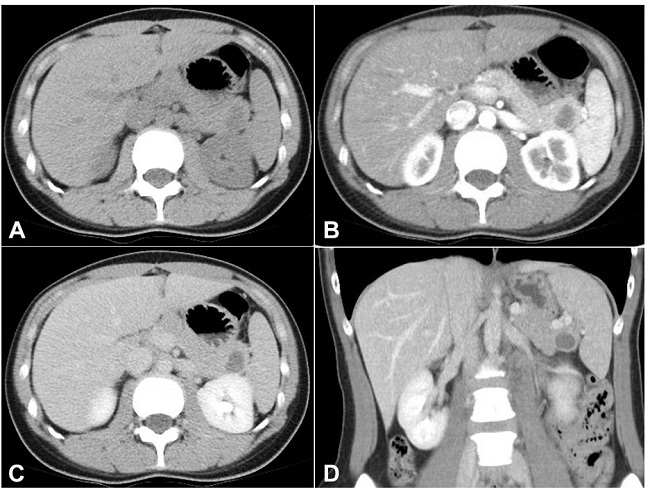

A 28-year-old Chinese woman with an unremarkable past medical history was presented to the hospital with dyspepsia and epigastric pain. She underwent abdominal ultrasound, which revealed a simple cyst at the pancreatic tail measuring 1.4 x1.7 x1.5cm in size, with no internal septa or solid area. A subsequent magnetic resonance imaging revealed a well-defined solitary unilocular cystic lesion in the pancreatic tail region, measuring up to 2.34 cm. There was a small mural nodule in its dependent portion and a minimal enhancement at its thin wall without significant enhancement of the mural nodule. There was no vascular invasion, definite communication with the non-dilated pancreatic duct, or lymphadenopathy. A contrast-enhanced computed tomography (CT) was also performed to further characterize the lesion, which revealed a 1.5 x 1.8 x 1.4 cm mildly lobulated, hypodense, and unilocular cyst in the tail of the pancreas. It showed no internal septation or calcification. The pancreatic duct was not dilated (Figure 1). The radiological differential diagnoses were mucinous cystic neoplasm, cystic form of solid pseudopapillary tumor or mucinous cystadenoma.